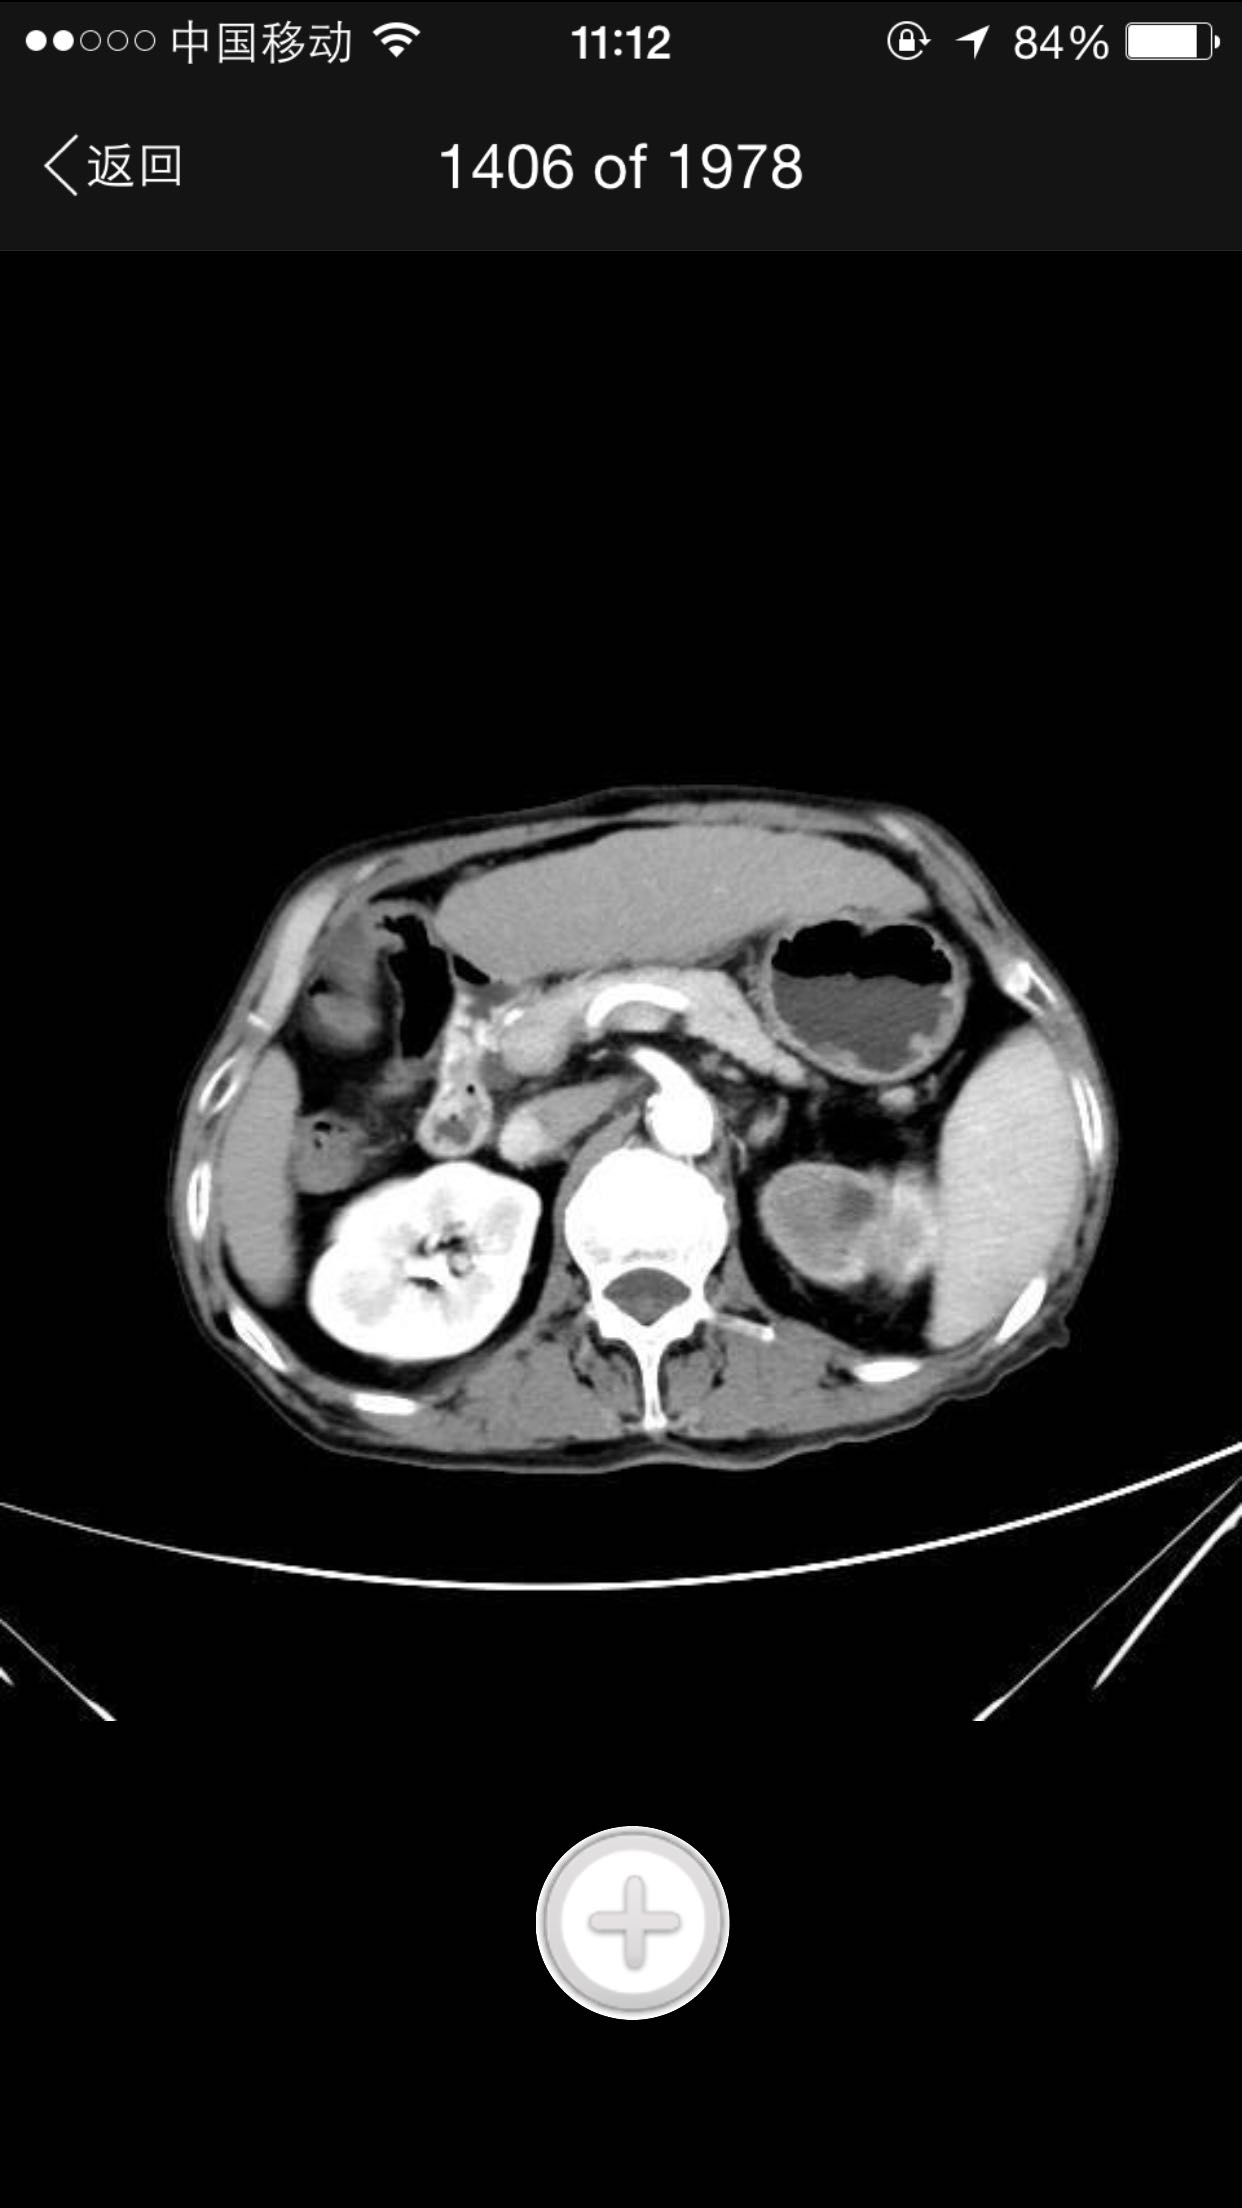

排尿困难,尿潴留入院。诊为前列腺增生症,拟行手术治疗。完善术前检查,泌尿系CT检查发现左肾占位,左肾结石并左肾重度积水,左肾萎缩等。既往患者肺结核病史,服药控制半年余。

查体:腹平软,无压痛及反跳痛,无肾区叩痛,肛诊前列腺明显增大,中央沟消失,无硬结,无压痛。术前强化CT提示左肾癌。

术前诊断:1、左肾癌2、左肾结石3、左肾积水4、左肾萎缩5、前列腺增生6、肺结核 入院后完善检查,拟行TURP,因发现左肾癌,改为先行肾手术。患者左肾癌,同时左肾结石,肾萎缩,决定行根治性肾切除,拟腹腔镜下手术,患者家属不同意,改开放手术,全麻下行根治性左肾切除。术后剖开标本如下图,肿瘤位于肾上极,中间黑色为结石。